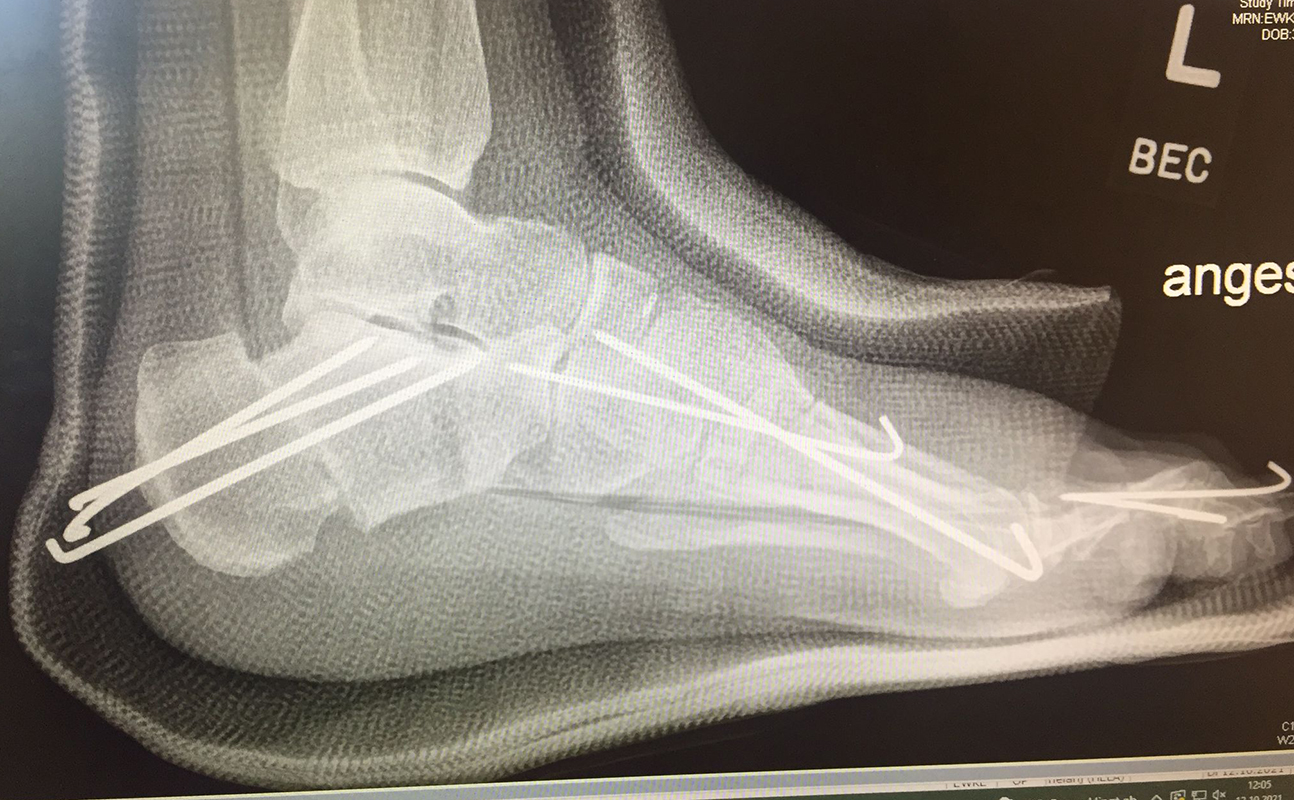

Zusätzlich schränken Wachstumsfugen die Wahl der Osteosynthese ein. Eine die Fuge kreuzende Osteosynthese ist ausschließlich mit Kirschner-Drähten möglich (Abb. 3).

Abb. 3 a-j: Beispiel einer Calcaneusverschiebeosteotomie mit offenen Wachstumsfugen und der entsprechenden Osteosynthese mit Kirschner Drähten. Lokalisation der Osteotomie (a), Lage der Fräse (b-d), Drahtlage mehrere Ansichten (e-h), Heilung der Osteotomie 4 Wochen postoperativ und Entfernung der Drähte (i-j).